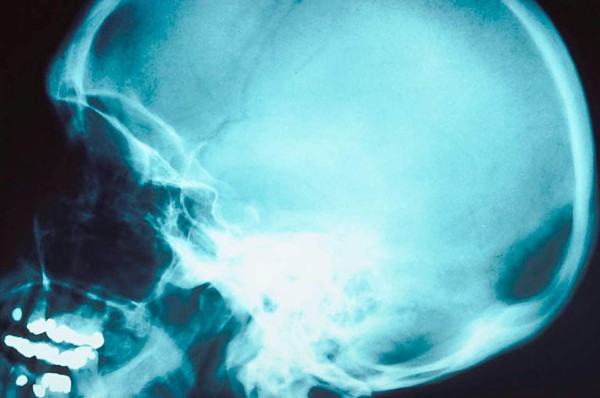

Un brillante alumno de la Universidad de Sheffield, de un coeficiente intelectual elevadísimo, acudió al médico universitario, el Profesor John Lorber, por un dolor de cabeza.

El doctór observó que su cabeza era algo más grande que lo normal, se dejó llevar por la curiosidad y le realizó un scan cerebral.

Los resultados arrojaron algo sorprendente: el estudiante, que estaba apunto de graduarse en Matemáticas, presentaba un cuadro crónico de hidrocefalia que le había borrado casi por completo la materia cerebral, reducida a un milímetro de tejido cubriendo la cima de su columna vertebral.